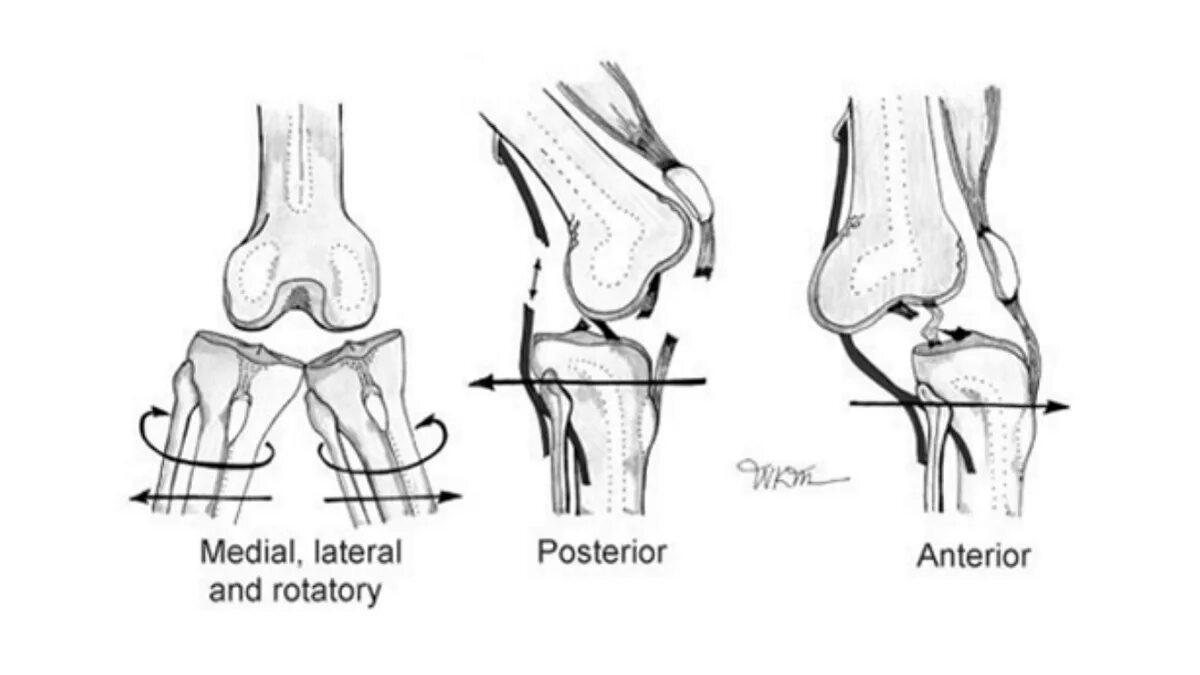

Смещение колена